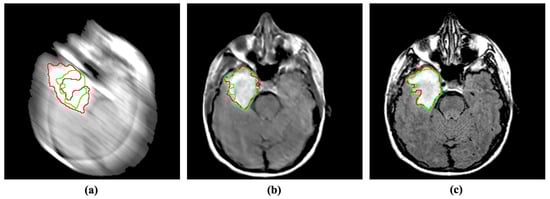

4.2.2. Detection

Similar to segmentation, abnormality detection is another widely used application in CAD. Such detection methods predict the region of abnormal issues or foreign bodies in a given medical image. Blind motion blurs can deteriorate the performance of such deep networks as well. We evaluated the performance of SOTA Mask R-CNN [37] with blurs in brain tumor detection. Despite being a well establish detection method, Mask R-CNN substantially suffers from blurs in the input image. Inversely, the proposed MID method can help the detection model by enhancing and removing blurs from the given input, as shown in Figure 7.

Figure 7. Incorporating the proposed method for deblurring medical images can improve the performance of abnormality detection. The red and green regions represent the area segmented by the deep model and the actual (ground-truth) affected region. (a) Blurry image + Mask R-CNN [37]. (b) Deblurred obtained by proposed method + Mask R-CNN [37]. (c) Reference image + Mask R-CNN [37].